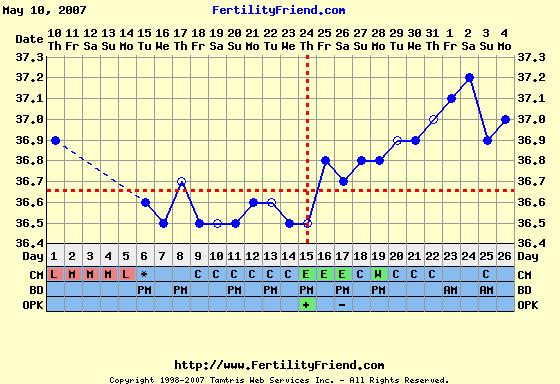

A hom továbbra is tartja a 36,8 -at. Se fel, se le. De már érzem, hogy fájdogál a hasam. Remélem nem a mensit jezi. Tegnap este érzetem egy kis hányingert, de már nem tulajdonítok neki jelentoséget, mert az elmúlt hónapokban is így éreztem.

Orulok, hogy a doki mindent redben talált. A táblázatból kivehetnéd a májusi programot, és helyette mehet június 11-e tesztelés. Akkor lesz a 20. DPO, feltéve ha eljutok odáig

Jobbulást kívánok. Nagyon szépen alakul a gorbéd, jó magasan van, akárcsak Krisztinkának. Nekem most valahogy nem akar feljebb menni.